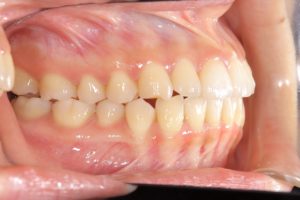

【動的治療終了時】

スプリントの期間も合わせると約3年で歯並び、噛み合わせともにしっかり整いました。

この状態がキープできるようリテーナー(保定装置)に切り替え、保定期間に入ります。